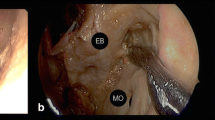

Ventral brainstem space

This most medial space was hardly accessible through the straight, ventral endoscopic transorbital trajectory. However, only by means of a 30° lens, the abducens nerve was appreciated as it entered the cavernous sinus from Dorello’s canal. Additionally, the basilar trunk at the midline gives origin to the anterior-inferior cerebellar artery (Fig. 12).

The ventral brainstem area can be showed via the transorbital approach. The abducens nerve can be seen in the cavernous sinus (a) entering from the Dorello’s canal (b, 30° angle endoscope turned medially). The anterior-inferior cerebellar artery coming from the basilar artery trunk can be appreciated by means of a 30° endoscope (c). csICA cavernous internal carotid artery, VI abducens nerve, V trigeminal nerve, GG gasserian ganglion, BA basilar artery, aica anterior-inferior cerebellar artery, Cl clivus, Pons pons portion of the brainstem, PSL petrosphenoid ligament. *Dorello’s canal